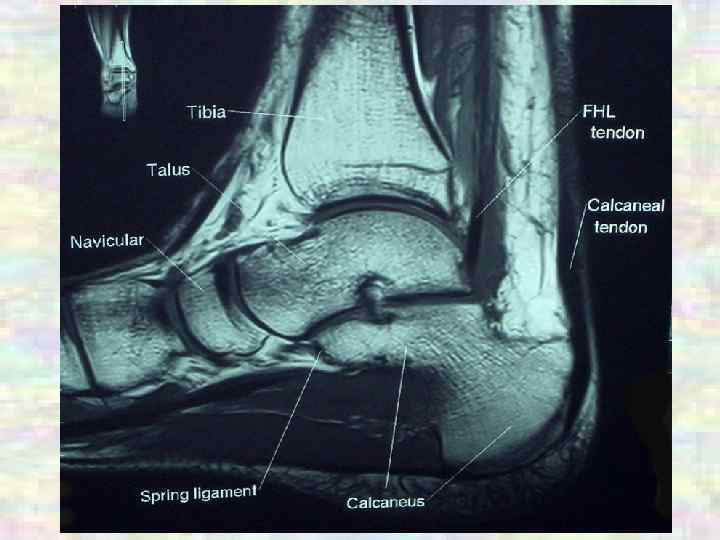

СУСТАВЫ Суставы нижней конечности Межплюсневые ü Подтаранный: цилиндрический, одноосный, малоподвижный (скольжение) ü Таранно-пяточно-ладьевидный: шаровидный, многоосный, малоподвижный (супинация, пронация) ü Межплюсневые: плоские, малоподвижные (супинация, пронация) ü Плюснефаланговые: эллипсоидные, двухосные (сгибание, разгибание – общий объем около 90°; приведение, отведение, движение большого пальца) ü Межфаланговые суставы стопы: блоковидные, одноосные (сгибание, разгибание, движения II-IV пальцев)